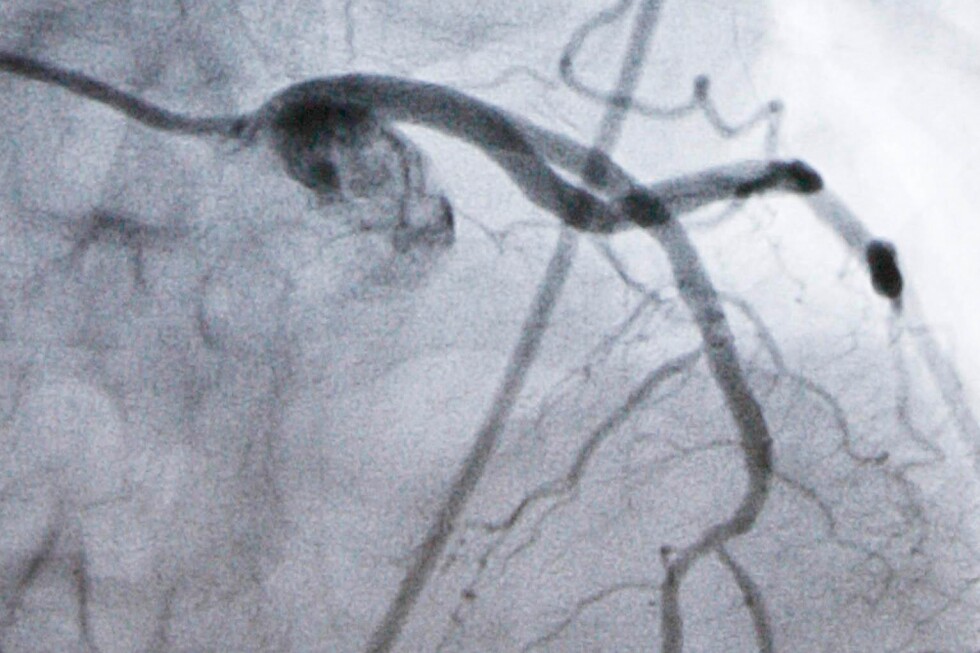

A monitor shows an artery during a catheterization lab heart procedure in Burlington, Vt., Tuesday, Sept. 23, 2008. (AP Photo/Toby Talbot, File) Add AP News as your preferred source to see more of our stories on Google. Share (function () { const counter = document.getElementById("scrollToComments"); const HEADER_OFFSET = 120; function findCommentsModule() { return document.querySelector('.vf3-comments, vf-conversations, '); } function maybeShowCounter() { if (findCommentsModule()) { counter.style.display = "inline-flex"; } else { counter.style.display = "none"; } } // Show only when Viafoura is present maybeShowCounter(); // Watch DOM for late loads const observer = new MutationObserver(maybeShowCounter); observer.observe(document.documentElement, { childList: true, subtree: true }); // Scroll action counter.addEventListener("click", function () { const el = findCommentsModule(); if (!el) return; const top = el.getBoundingClientRect().top + window.scrollY - HEADER_OFFSET; window.scrollTo({ top, behavior: "smooth" }); }); })(); .thin-line-button { display: inline-flex; align-items: center; justify-content: center; border: 1px solid #ccc; height: 30px; padding: 0 10px; cursor: pointer; border-radius: 5px; background: none; text-align: center; font-size: 1.4rem; font-weight: 700; white-space: nowrap; flex-shrink: 0; color: inherit; transition: none; /* Remove animation effect */ } .thin-line-button { color: #000; background: white; } /* Remove hover effect */ .thin-line-button:hover { border: 1px solid #ccc; } .comment-icon { width: 20px; height: 20px; min-width: 20px; min-height: 20px; flex: 0 0 20px; object-fit: contain; display: inline-block; } .Page-actions-commentCounter .embed-caption { display: none; } .vf-comments-count.vf-is-logged-in { margin-left: 4px; } WASHINGTON (AP) — A new kind of pill sharply reduced artery-clogging cholesterol in people who remain at high risk of heart attacks despite taking statins, researchers reported Wednesday. It’s still experimental but the pill helps rid the body of cholesterol in a way that today can be done only with injected medicines. If approved by the Food and Drug Administration, the pill, named enlicitide, could offer an easier-to-use option for millions of people. Statins block some of the liver’s production of cholesterol and are the cornerstone of treatment. But even taking the highest doses, many people need additional help lowering their LDL, or “bad,” cholesterol enough to meet medical guidelines. In a major study, more than 2,900 high-risk patients were randomly assigned to add a daily enlicitide pill or a dummy drug to their standard treatment. The enlicitide users saw their LDL cholesterol drop by as much as 60% over six months, researchers reported in the New England Journal of Medicine. There are other pills that patients can add to their statins “but none come close to the degree of LDL cholesterol lowering that we see with enlicitide,” said study lead author Dr. Ann Marie Navar, a cardiologist at UT Southwestern Medical Center. That benefit dropped only slightly over a year, and there was no safety difference between those taking the pill or placebo, researchers found. One caveat: The pill must be taken on an empty stomach. Heart disease is the nation’s leading cause of death and high LDL cholesterol, which causes plaque to build up in arteries, is a top risk factor for heart attacks and strokes. While an LDL level of 100 is considered fine for healthy people, doctors recommend lowering it to at least 70 once people develop high cholesterol or heart disease — and even lower for those at very high risk. Statin pills like Lipitor and Crestor, or their cheap generic equivalents, are highly effective at lowering LDL. For additional help, some powerful injected drugs work differently, blocking a liver protein named PCSK9 that limits the body’s ability to clear cholesterol from blood. Yet only a small fraction of people who could benefit from PCSK9 inhibitors use them. While prices for the costly shots have dropped recently, patients still may dislike administering shots and Navar said they’re more complex for doctors to prescribe. Merck funded Wednesday’s study, which provides some of the final data needed to seek FDA approval of enlicitide. The FDA has added the drug to a program promising ultra-fast reviews. The research offers “compelling evidence” that the new pill lowers cholesterol about as much as those PCSK9 shots, Dr. William Boden of Boston University and the VA New England Healthcare System, who wasn’t involved with the study, wrote in the journal. Boden cautioned there’s no data yet showing the pill’s cholesterol-reduction translates into fewer heart attacks, strokes and death. That takes much longer than a year to prove. Merck has a study of more than 14,000 patients underway to tell. The Associated Press Health and Science Department receives support from the Howard Hughes Medical Institute’s Department of Science Education and the Robert Wood Johnson Foundation. The AP is solely responsible for all content.